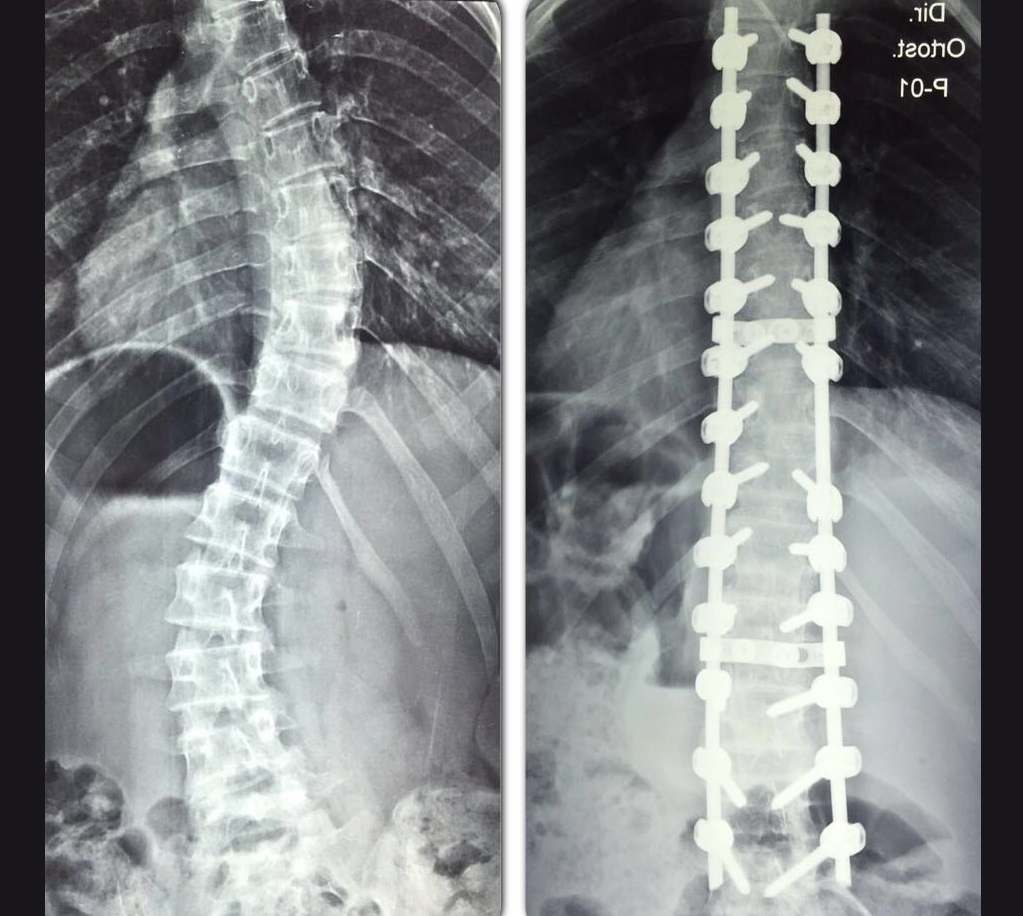

![]() |

| Correção da curvatura da coluna vertebral de alagoana melhorou qualidade de vida de alagoana (Crédito: Cortesia/Arquivo pessoal) |

Com o filho próximo de completar 18 anos, em dezembro de 2013, Anna aproveitou um convênio da empresa onde trabalhava e passou por uma cirurgia para corrigir a curvatura de 84 graus da coluna vertebral. “Tive mesmo de fazer a cirurgia e não voltar mais, mas o procedimento foi bem sucedido”, lembrou a alagoana portadora de escoliose idiopática - adquirida entre 0 ano e a maturidade.

A curvatura não foi completamente corrigida, mas a técnica em enfermagem está satisfeita e fala com muito entusiasmo sobre as mudanças sentidas após a cirurgia. “Não corrigiu 100% porque deixei para operar um pouquinho velha, mas posso dizer que melhorei 99%. Mudou muita coisa, minha autoestima, respiração e a reputação, praticamente quase tudo”, relatou.

“Não exerço minha profissão por conta da minha coluna. Não posso pegar muito peso porque tenho 18 parafusos e duas hastes na coluna. Então no momento não trabalho”, finalizou a alagoana, que é a única dos oito irmãos portadora de escoliose na família.

| Procedimento cirúrgico corrigiu quase toda a curvatura da coluna vertebral de Anna Honório da Silva (Crédito: Cortesia/Arquivo familiar) |